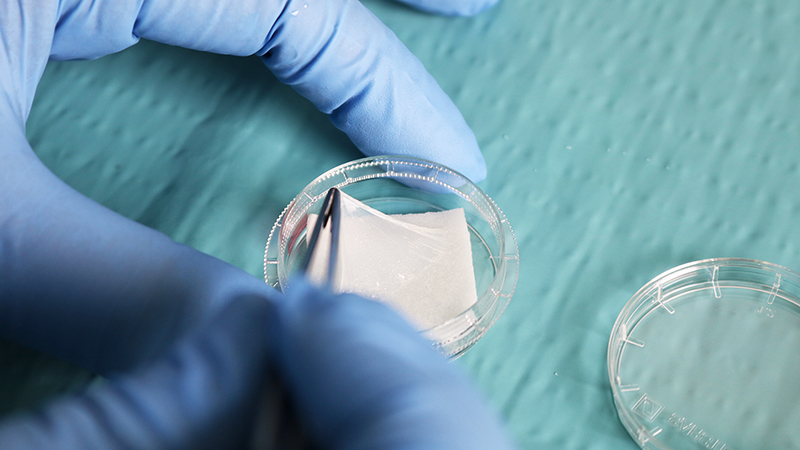

Hofmann, N.; Salz, A.-K.; Kleinhoff, K.; Möhle, N.; Börgel, M.; Diedenhofen, N.; Engelmann, K.. AmnioClip-Plus as Sutureless Alternative to Amniotic Membrane Transplantation to Improve Healing of Ocular Surface Disorders. Transplantology 2021, 2, 425-432. https://doi.org/10.3390/transplantology2040040

Odet, S., Louvrier, A., Meyer, C., Nicolas, F. J., Hofman, N., Chatelain, B., Mauprivez, C., Laurence, S., Kerdjoudj, H., Zwetyenga, N., Fricain, J.-C., Lafarge, X., Pouthier, F., Marchetti, P., Gauthier, A.-S., Fenelon, M., Gindraux, F. (2021). Surgical Application of Human Amniotic Membrane and Amnion-Chorion Membrane in the Oral Cavity and Efficacy Evaluation: Corollary With Ophthalmological and Wound Healing Experiences. Front. Bioeng. Biotechnol. 9:685128. doi: 10.3389/fbioe.2021.685128

N. Hofmann, N. Möhle, K. Becke, K. Engelmann, M. Börgel: Expert and user feedback on the application of AmnioClip plus. Vortrag auf dem XXXII Annual Meeting of the European Eye Bank Association, EEBA, 16-18 January 2020, Hannover

O. Pogozhykh, N. Hofmann, O. Gryshkov et al.: Repeated Freezing Procedures Preserve Structural and Functional Properties of Amniotic Membrane for Application in Ophthalmology. International Journal of Molecular Sciences. 2020;21(11):E4029. Published 2020 Jun 4. doi:10.3390/ijms21114029

N. Hofmann, A.-K. Salz, K. Becke, N. Möhle, M. Börgel, N. Diedenhofen, K. Engelmann. AmnioClip-plus – die nahtlose Amnionmembranbehandlung. OPHTHALMO-CHIRURGIE 2020;32(4): 179-183.

L.-M. Sara, T. Kern, N. Hofmann, O. Pogozhykh, C. Framme, M. Börgel, C. Figueiredo, B. Glasmacher, O. Gryshkov: Human Amniotic Membrane: A review on tissue engineering, application, and storage. Journal of Biomedical Materials Research Part B: Applied Biomaterials Published Dec 2 2020. DOI: 10.1002/jbm.b.34782